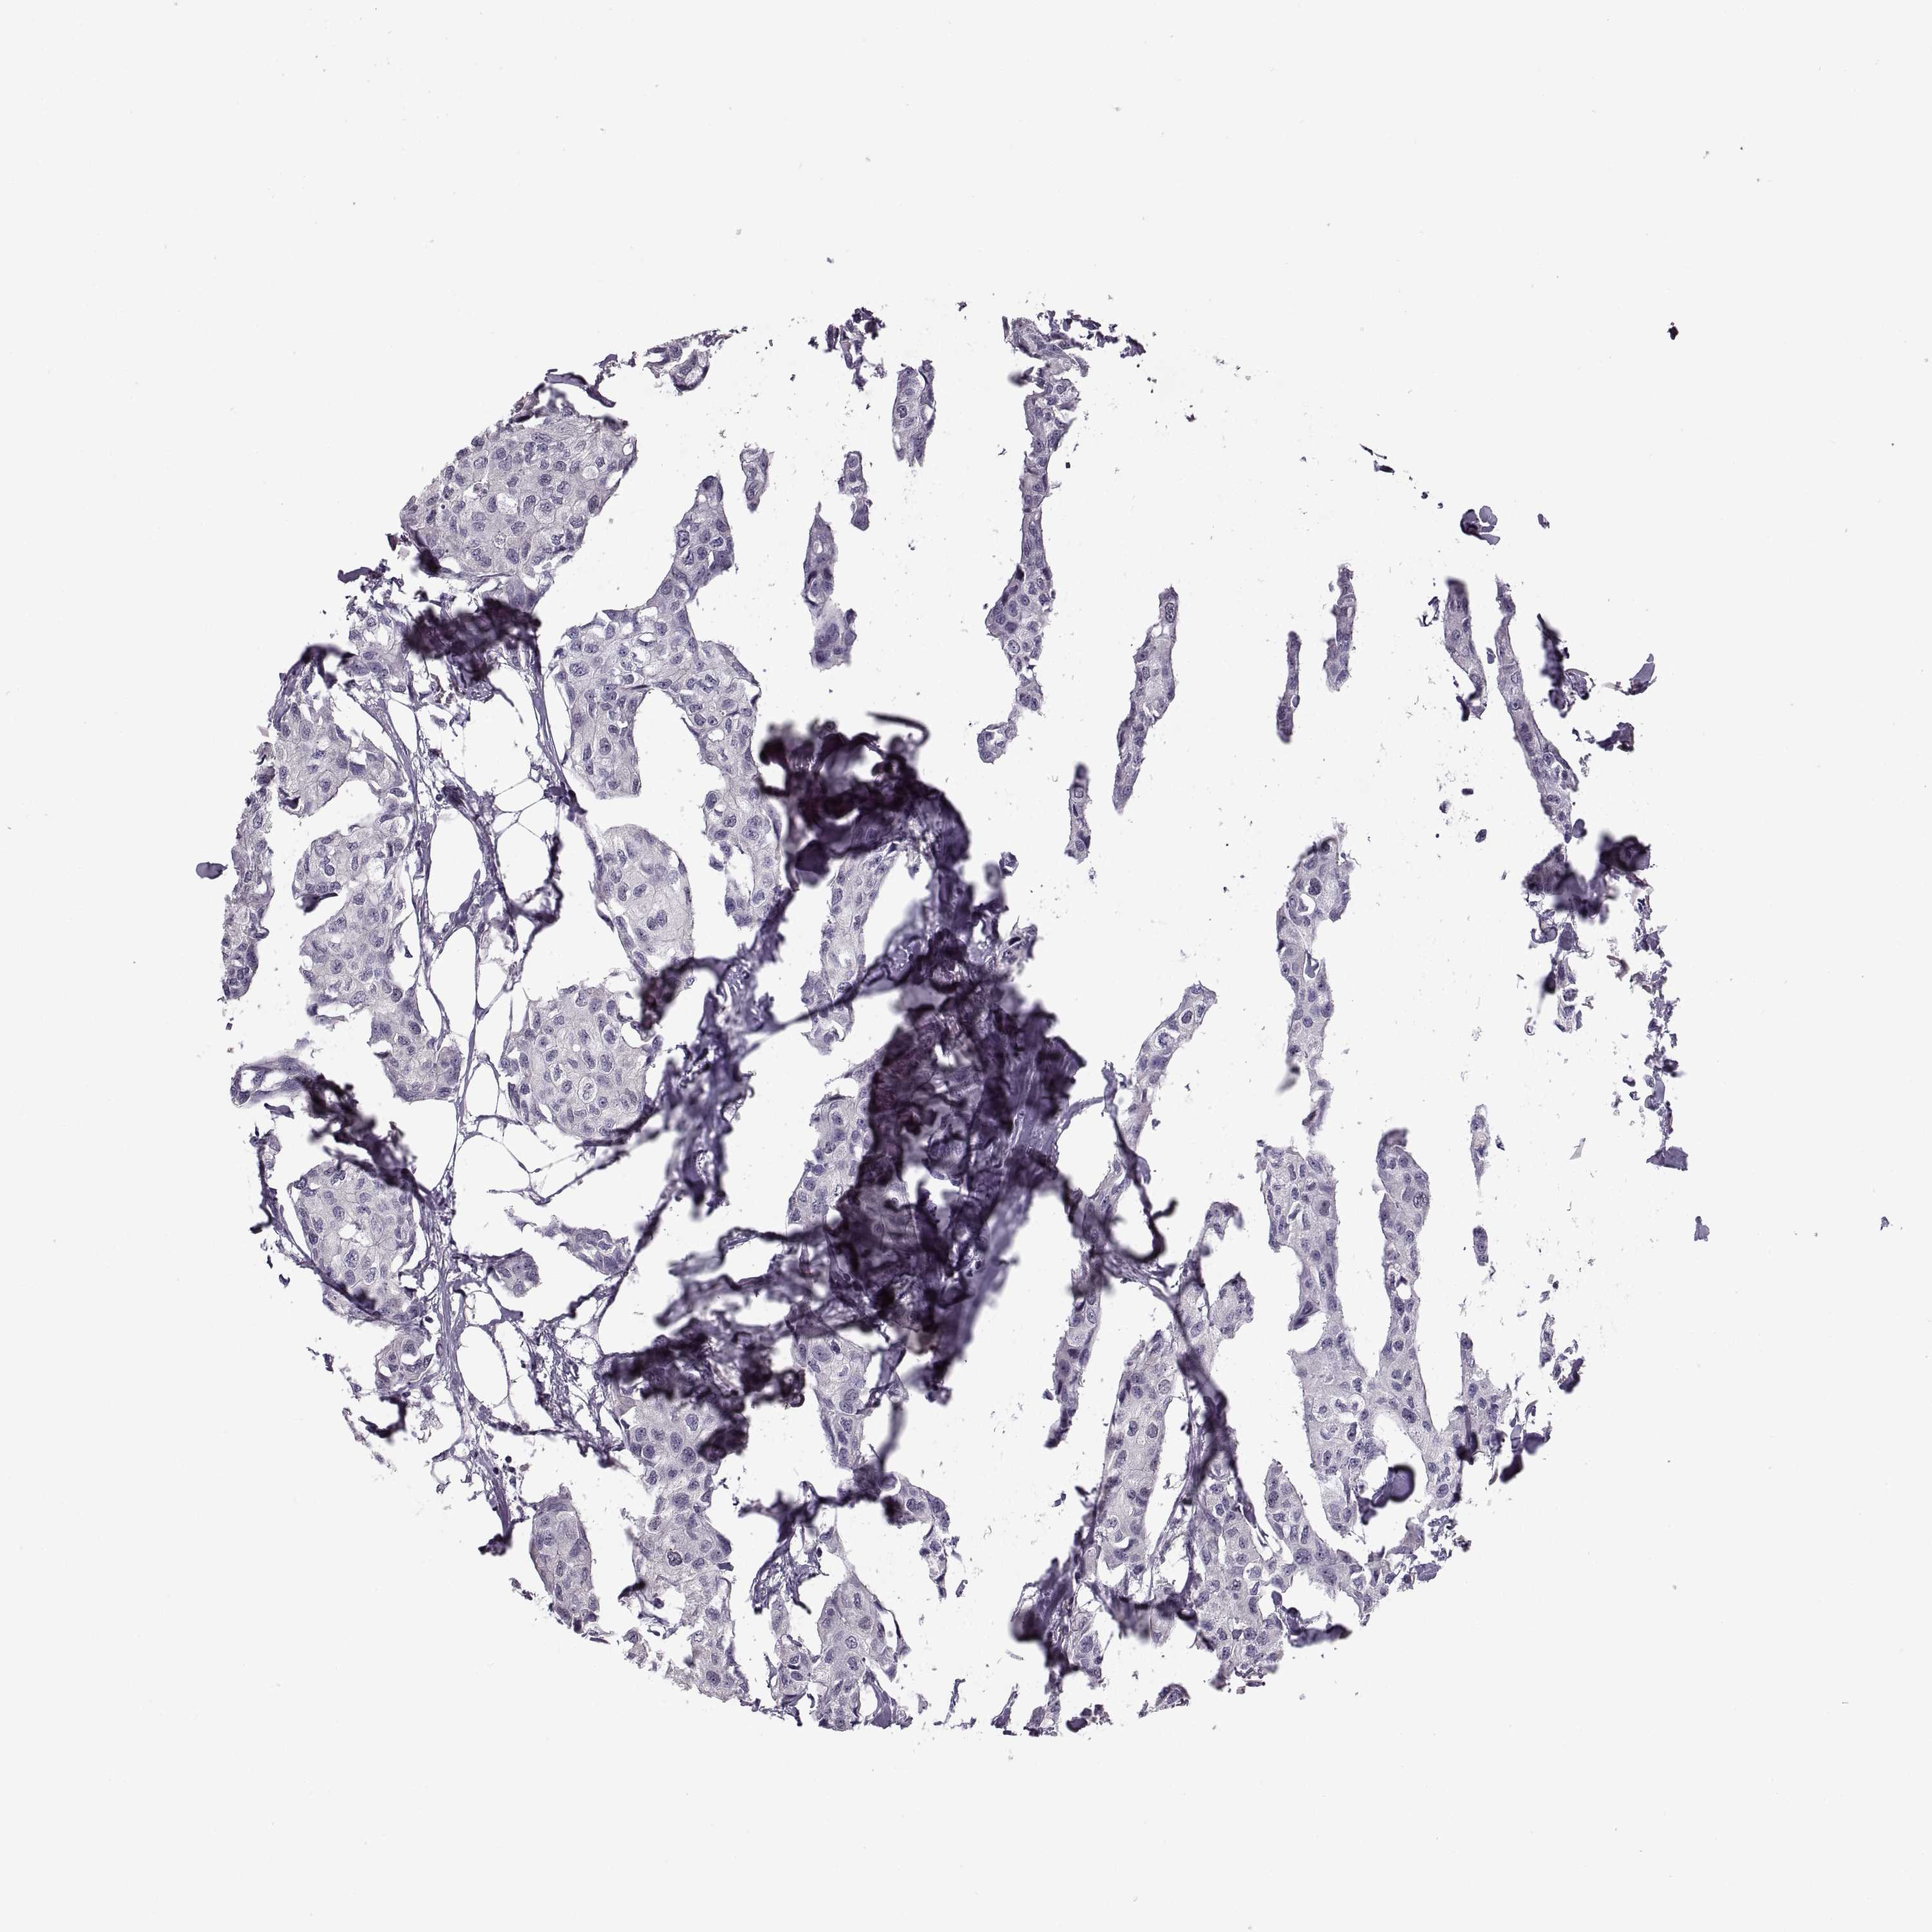

BRCA TCGA BRCA VALIDATION PROTEIN EXPRESSION